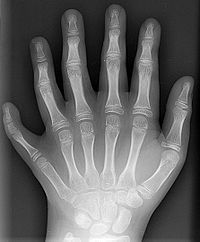

多指(趾)症(たししょう)とは、手足の先天性の形状異常のひとつであり、指(足の場合は趾)が分離形成される段階で、1本の指(趾)が2本以上に分かれて形成される疾患のことである。

結果として手足の指の数が6本以上となる。反対に、指の数が少ないのを欠指(趾)症という。手足の先天性異常では比較的多くの割合を占め、様々な症候群に合併する。

多指症のX線写真(左手) 骨格には不完全な部分が見られない。

過剰な指(趾)が痕跡的に突き出るもの、細い茎でぶらぶらする指(趾)がつながっているもの(浮遊型)、完全な指(趾)の形を示すものまで見られさまざまである。

人種的には黒人に多く見られるが、どの人種にも見られ、日本人では手指の場合は拇指(親指)に、足趾の場合は第V趾に多く見られる。